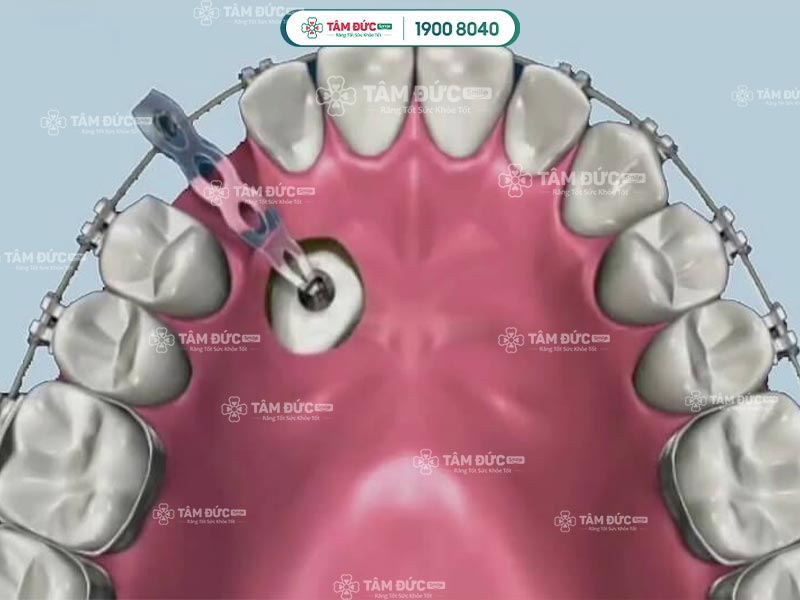

- Niềng răng: Là kỹ thuật chỉnh nha giúp răng dịch chuyển về vị trí chuẩn. Phương pháp này chỉ có thể thực hiện khi cung hàm còn đủ khoảng trống cho răng mọc.

Niềng răng nanh mọc ngầm